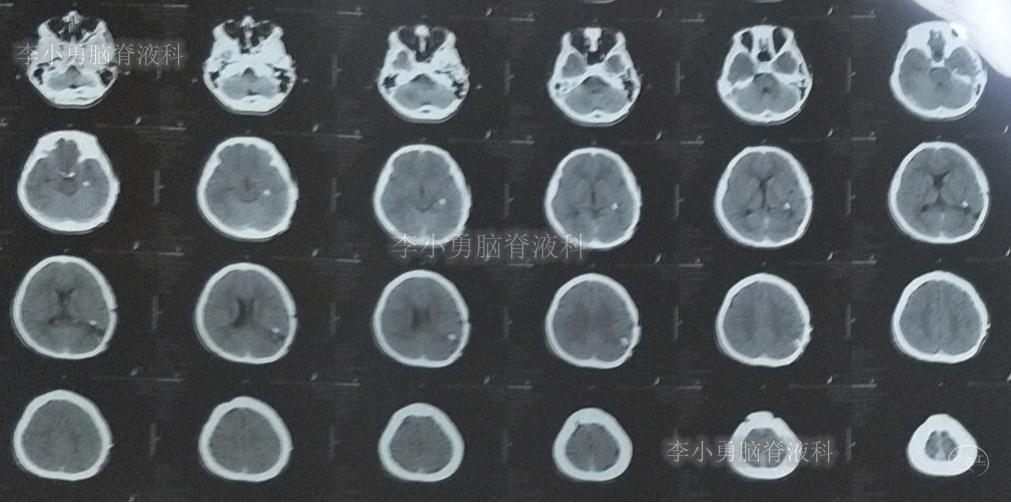

出院后2个月即2019年12月9日,复查头颅CT示脑室系统较出院时无明显变化(图-25);但患者记忆力仍差。

图-25:2019年12月9日头颅CT

出院后9个月即2020年7月6日,再次复查头颅CT(图-26):未见异常。家属叙述:肢体活动正常,记忆力较前有些改善但较同龄人仍差,已重返校园(图-27)。

图-26:2020年7月6日头颅CT:未见异常